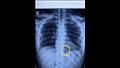

وأضاف الجزار أن خطورة وصعوبة الجراحة في هذه الحالة تمثلت في وجود الإبرة في الظهر مما يستدعي قلب المريض على بطنه بعد تخديره وهو أمر صعب وخطير وطبيا والصعوبة الثانية في عدم معرفة مكان الإبرة بالضبط في الجسم مما تتطلب استخدام جهاز أشعة داخل غرفة العمليات مما يسهل تحديد المكان واستخراجها، الثالثة تعرض الإبرة للصدأ فاضطررنا لاستخراجها على هيئة قطع.

وكان فريق جراحي بمستشفى بنها الجامعي بمحافظة القليوبية بقيادة الدكتور محمد أحمد الجزار استشاري جراحة القلب والصدر بمستشفى بنها الجامعي قد نجح فى استخراج إبرة تنجيد دخلت عن طريق الخطأ فى ظهر مريض خلف القفص الصدري مباشرة والتى ظلت بمكانها مدة عامين حيث جرى إجراء جراحة بفتح جراحي صغير 3 سم، استخراج إبرة تنجيد دخلت بطريق الخطأ فى ظهر مريض خلف القفص الصدري مباشرة حيث تركها المريض لمدة سنتين خوفا من إجراء العملي.

ووفق بيان المستشفى فقد جرى حجز المريض بالقسم وتجهيزه لعملية سريعة، جرى فيها الاستعانة بجهاز الأشعة الملحق بغرف العمليات (C-arm)، حيث تم تحديد مكان الإبرة والفتح الجراحي عليها مباشرة، واستخراجها بنجاح ،ولكن علي هيئة قطع منكسرة بسبب الصدأ، نظرا لبقائها طوال هذه المدة.